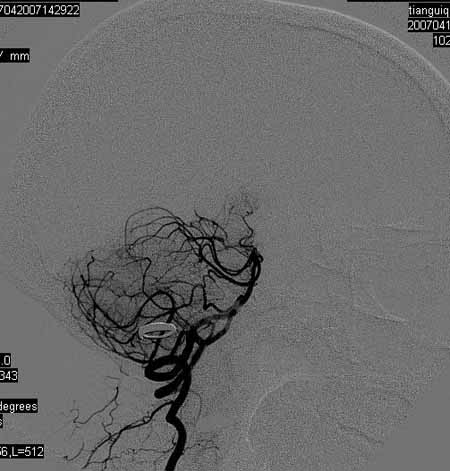

标题: DSA0093:脑血管造影

女,63岁,左侧额、枕叶脑梗塞。

右肾动脉及左颈内动脉起始部狭窄(考虑动脉硬化引起的),大脑中动脉分支减少.